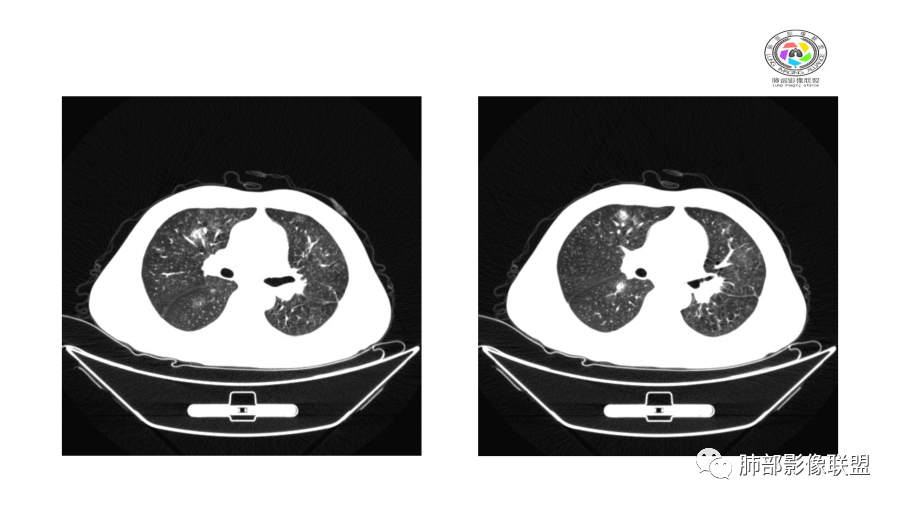

中年男性,高血压,肾功能衰竭,贫血病史,尿潜血阳性。3.8双肺野多发斑片磨玻璃实变影,结节影,边缘模糊,周围有晕征,内见支气管充气征,主要沿支气管血管束分布,部分胸膜下分布,3.12号病灶有吸收好转,4.8号斑片实变影基本吸收,主要沿支气管血管束分布结节影,边缘平直收缩,4.28病灶大部分吸收好转,双肺支气管血管束增粗,有少量结节影。考虑ANCA相关性血管炎可能性大,第一次片子觉得隐球菌不排除,但是后面没有抗真菌治疗就吸收了,觉得隐球菌可能性不大。

胸部CT:双肺多发实性斑片影,散在GGO。实性斑片周围可见晕征、边缘模糊不清,病灶于肺外围区域优势分布。肺门区血管影增粗,支气管套袖,目测肺动脉增粗。3月、4月复查肺内实性斑片病灶呈游走性,此起彼伏。

10天后:病灶继续吸收好转

伴随少量胸水

应该与气道无关

符合间质、血管来源病变

此起彼伏